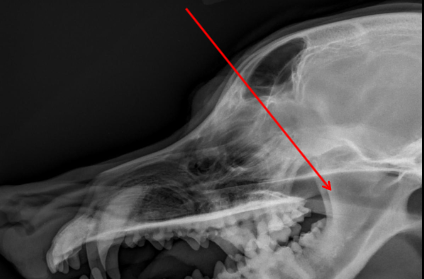

Tympanic Bulla

ID.

Horizontal Ear Canal

Occipital Condyles

Temporomandibular Joint